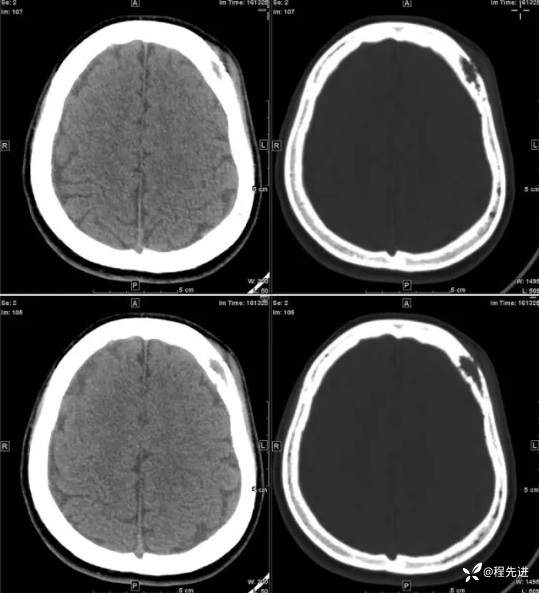

【患者信息】:女,31岁

【主诉】:发现头部肿物1月余

【现病史及既往史】:患者自诉于1月前无明显诱因出现左额颞部肿块,大小约3*3cm,伴疼痛红肿发热,遂至我院外科门诊就诊考虑“局部感染”,予以对症治疗后,肿块疼痛红肿好转,但肿块无明显缩小。

【检查】:常规检验项目均(-)